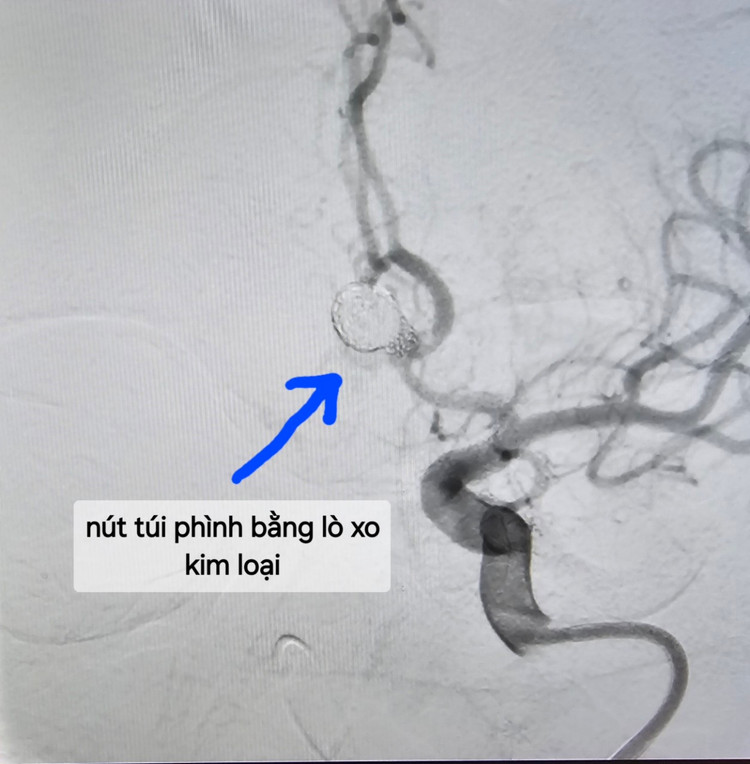

| Nút túi phình bằng lò xo kim loại - Ảnh BVCC |

- Nút túi phình mạch não: có thể can thiệp nút bằng sợi kim loại, hoặc phẫu thuật túi phình…